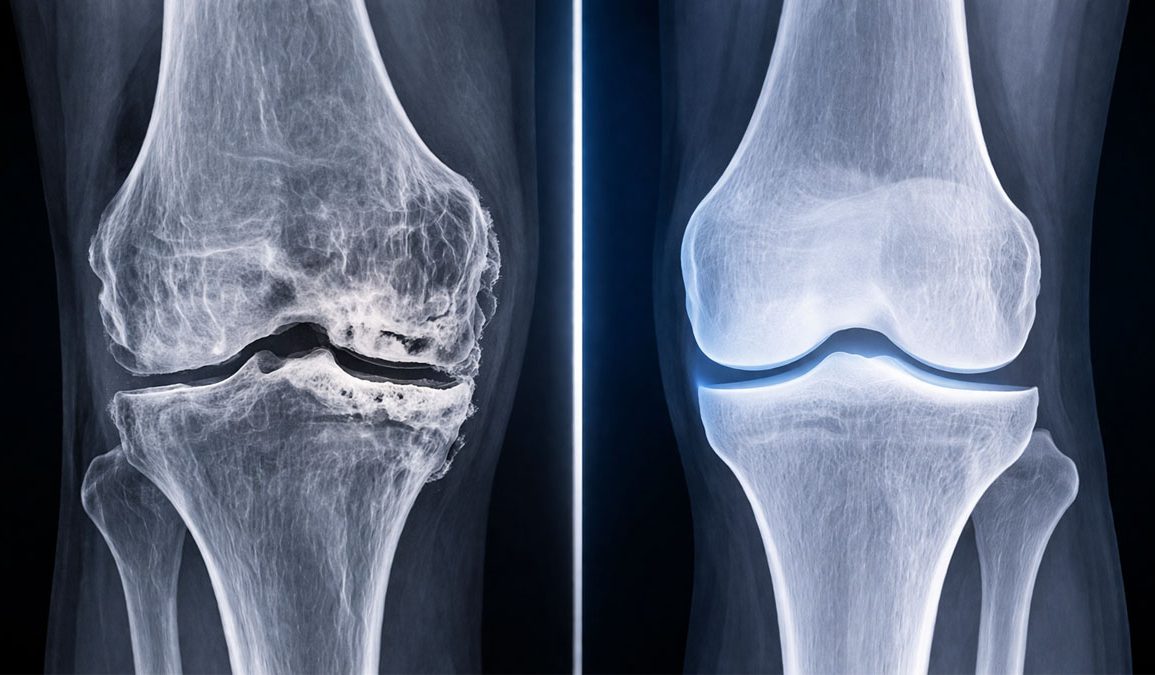

Osteoarthritis is one of the most common and debilitating conditions associated with aging and injury, affecting roughly 20 percent of the U.S. population. For decades, treatment options have been limited. Most approaches focus on managing pain or, in severe cases, replacing the joint entirely. Now, a new study led by Stanford Medicine offers a fundamentally different path forward.

Researchers have discovered that blocking a specific enzyme, known as 15-hydroxy prostaglandin dehydrogenase, or 15-PGDH, can actually reverse cartilage loss. This finding opens the door to therapies that do not just slow the disease but potentially restore damaged tissue.

The implications are significant. Current osteoarthritis treatments do not reverse damage. This approach could change that by directly targeting a mechanism linked to aging itself. Researchers describe 15-PGDH as a “gerozyme,” an enzyme that drives tissue aging.

By inhibiting this enzyme, the study concludes that cartilage regeneration can occur not only in animal models but also in human tissue. This positions the therapy as “a new therapeutic approach for OA that is readily amenable to translation to the clinic.”

If these findings hold up in further trials, they could mark a turning point in how joint disease is treated. Instead of managing decline, medicine may soon be able to restore what was lost.